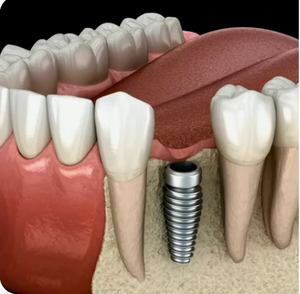

В большинстве случаев, зубные имплантаты являются золотым стандартом замещения отсутствующих зубов. Они могут быть установлены как в день удаления зубов, так и через длительное время после удаления зуба. И могут быть применены при отсутствии одного или нескольких зубов. Имплантация зубов достаточно быстрая и безболезненная процедура. Фактически, большинство людей считают, что установка имплантатов является более приятной процедурой, чем удаление зуба. Мы никогда не оставим вас с видимым промежутком между зубами и всегда будем убеждаться, что ваша улыбка великолепно выглядит во время лечения.

Дентальные имплантаты.

Ииплантация — это процедура, доступная в нашей стоматологической клинике «Декадент». Имплантаты являются идеальным решением для замены одного или нескольких отсутствующих зубов. Предлагаемая нашей клиникой имплантация полностью восстановит жевательную эффективность.

Наши хирурги, имеющие все необходимые навыки и богатый опыт имплантации, гарантированно проведут операцию на максимально высоком уровне. Благодаря использованию передовых хирургических методов и материалов самого высокого качества, имплантаты зубов выглядят естественными и сохраняются в течение длительного времени.

Почему стоит выбрать дентальные имплантаты:

- Эстетика — выглядит как естественный зуб и через некоторое время вы забудете о том, что он является искусственным.

- Отсутствие необходимости препарирования соседних зубов — в отличие от мостов и протезов, имплантаты не требуют поддержки от других зубов.

- Предотвращение потери кости — предотвратит дистрофию кости и, следовательно, сохранит поддержку и структуру лица.

- Увеличение срока службы оставшихся зубов — имплантаты будут защищать оставшиеся зубы от чрезмерной нагрузки (путем равномерного распределения жевательной нагрузки) и воспрепятствуют перемещению, наклону и выдвижению зубов.

- Фиксация — имплантаты фиксируются во рту и не требуют снятия, как это было бы при использовании съемных протезов.

- Отсутствие чувствительности и необходимости в пломбах — имплантаты никогда не потребуют пломбирования или лечения корневых каналов и они никогда не будут чувствительны.